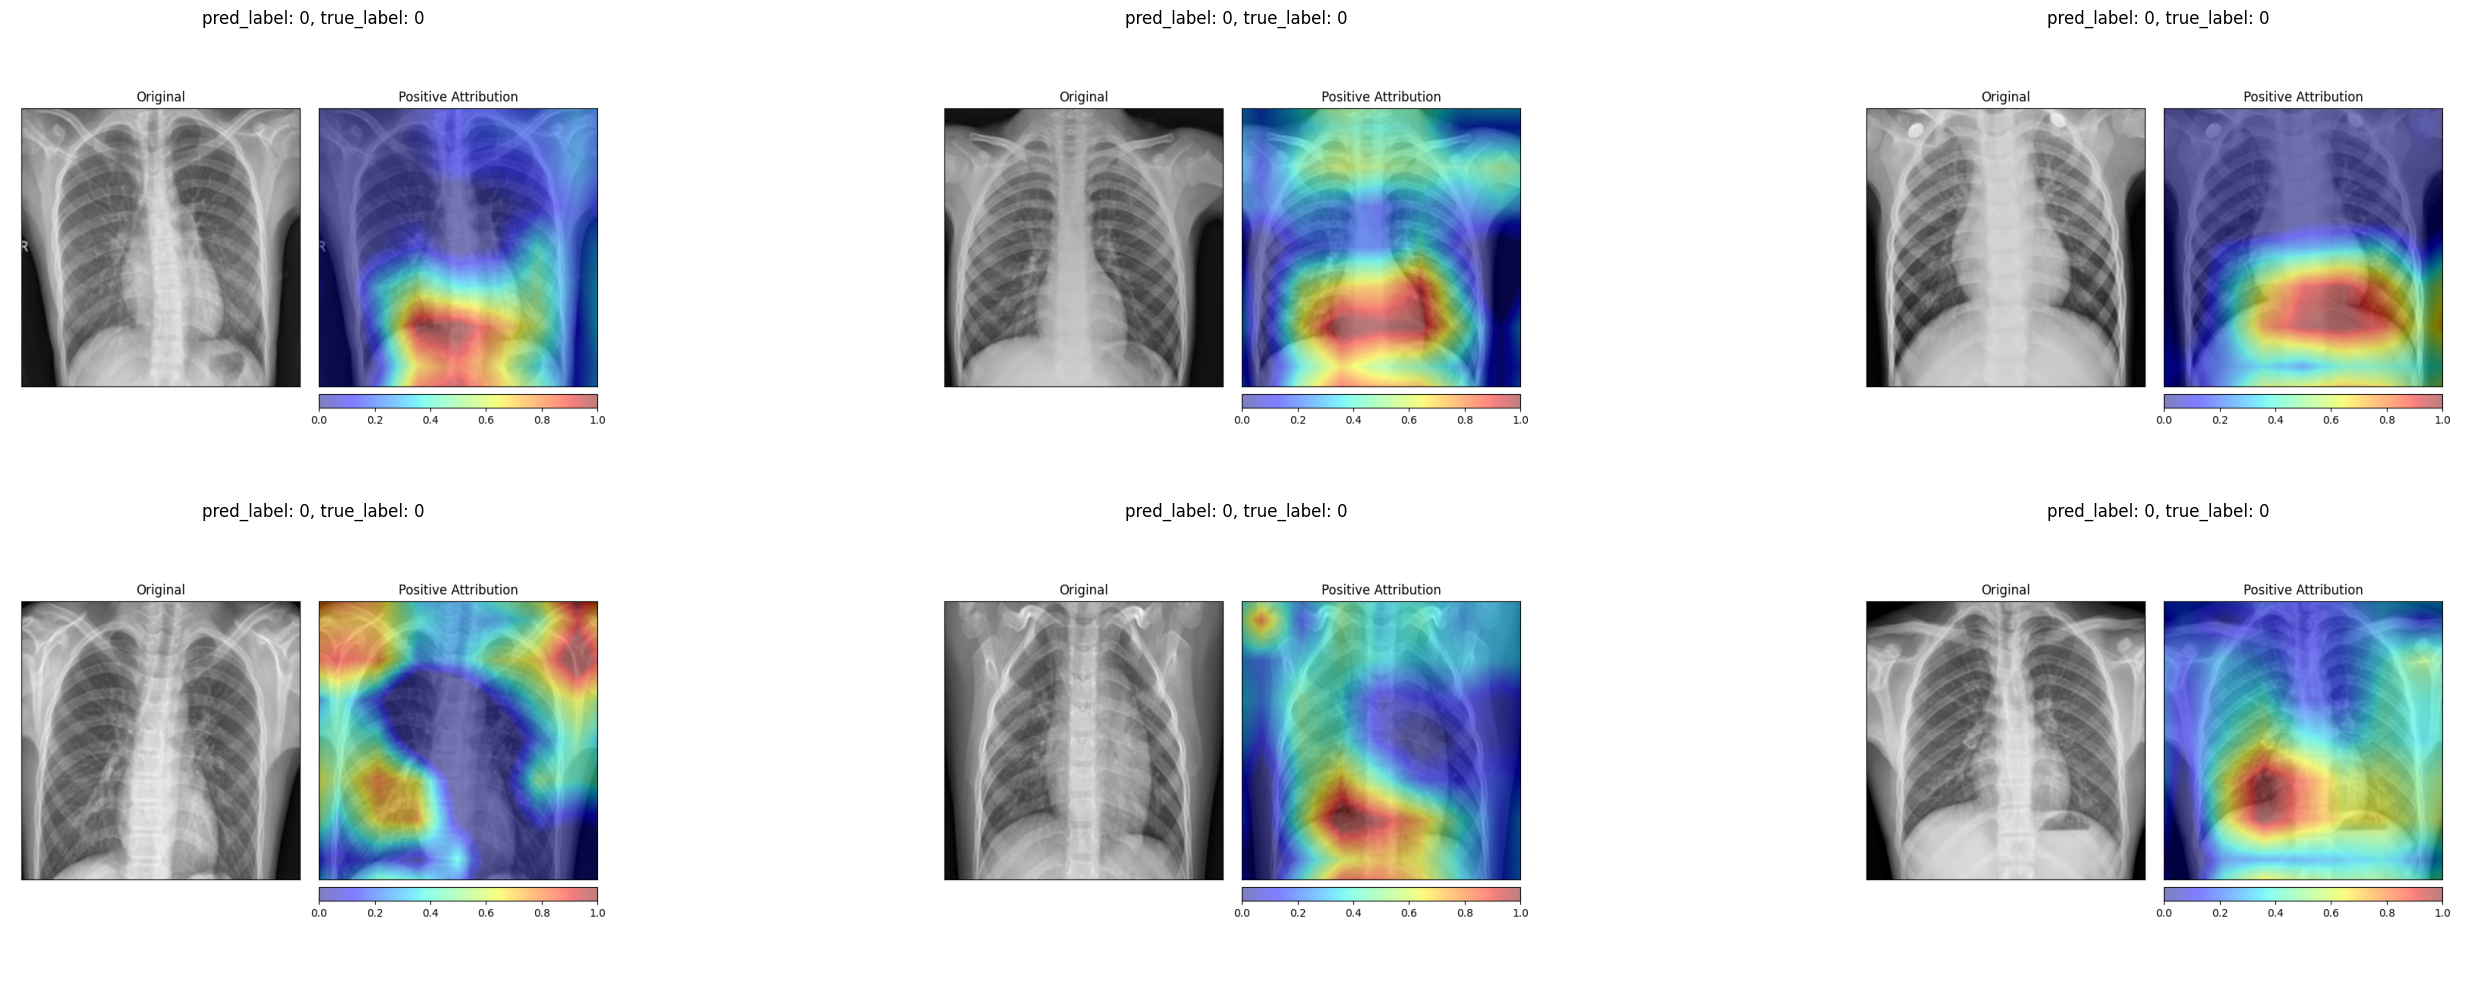

The attribution maps for healthy patients tend to highlight the lung fields and the spine in a relatively focused manner, consistent with the model confirming the absence of pathology in these regions.

For pneumonia patients, the attributions spread across a broader area of the chest, reflecting the diffuse nature of pneumonia opacities. The model does not focus on a single localized region but instead distributes importance across the entire affected area.

For healthy patients, the Grad-CAM heatmaps concentrate on the central and lower lung regions, highlighting areas where the model confirms normal tissue.

For pneumonia patients, the activation maps expand to cover broader regions of the chest, often focusing on the areas where opacities are visible in the original X-ray. In several examples, the strongest activations align precisely with the haziest regions of the lung fields.

4.3 Comparing the Two Methods

The two attribution methods tell a broadly consistent story. Both highlight the lung fields as the most decision-relevant region. Both show more diffuse attribution patterns for pneumonia cases and more localized patterns for healthy ones. The key difference is granularity. Integrated Gradients produces fine-grained, pixel-level attributions that can appear noisy, while Grad-CAM produces smoother heatmaps that are easier to interpret at a glance but lose fine spatial detail. For a radiologist who wants to quickly see where the model is “looking”, Grad-CAM is the more practical tool. For a researcher who wants to understand exactly which pixel intensities drive the output, Integrated Gradients provides more information.